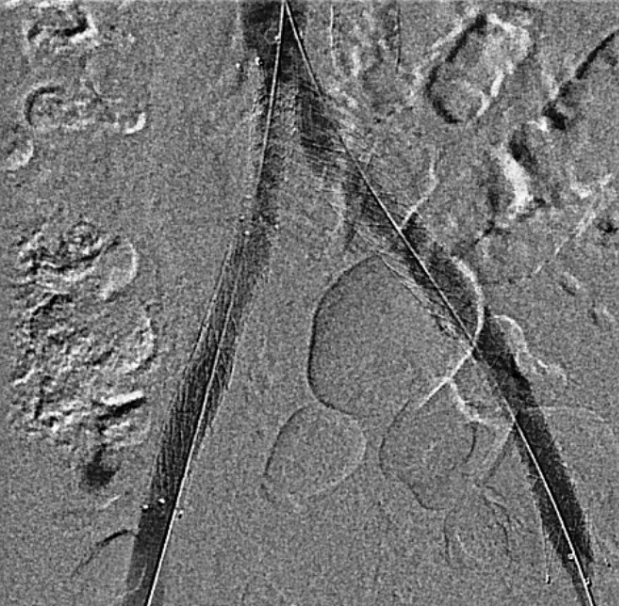

Venography showed occlusion of the right external and common iliac veins with collateral flow; popliteal and femoral veins were patent. A 6F sheath was placed in the right CFV, and a V-18 0.018 wire was advanced to the IVC. Attempts to traverse outside the prior left iliac-femoral stent for double-barrel reconstruction were unsuccessful, as the wire repeatedly entered the existing stent, likely due to complete apposition.The strategy was revised, and wiring into the IVC through a proximal stent strut was achieved. IVUS from the IVC to the RCFV confirmed severe compression at the right CIV ostium and proper wire position. A 10 ¡¿ 39 mm Abbott Omnilink balloon-expandable stent was deployed at the RCIV ostium and dilated to 10 atm. A kissing-balloon angioplasty was then performed with a 12 ¡¿ 40 mm Armada balloon from the LCIV and the RCIV balloon inflated simultaneously to 10 atm, restoring bifurcation geometry.A 14 ¡¿ 60 mm Bard Venovo stent was placed from the RCIV to the REIV and post-dilated with a 12 mm balloon to 10 atm. Final angiography showed widely patent, well-expanded stents with brisk antegrade flow into the IVC and no residual stenosis or thrombosis. Hemostasis was achieved with manual compression, and the procedure concluded without complications.

The patient achieved rapid clinical improvement with resolution of limb edema and remained free of recurrence under oral anticoagulation at follow-up.This experience highlights that in cases where conventional double-barrel iliocaval reconstruction is technically unachievable due to prior stent endothelialization or anatomic limitation, cross-strut recanalization combined with balloon-expandable stent implantation and kissing balloon angioplasty provides a feasible and durable alternative for iliocaval revascularization.